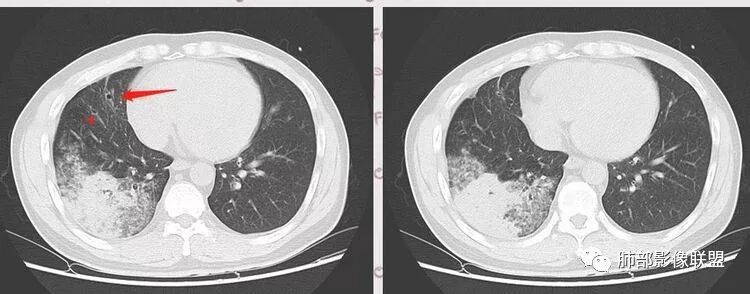

1.分布,你曾经说过一次,但是可能很多人没有听过,这边再次提出,就是如果是肺原发的,和支气管来的一个区别。这个我来找一下,稍后多说说。2.这个GGO到底是边界清楚还是不清楚。这个问题有一点主观,我觉得还蛮清楚,但是你说不清楚,有时候征象每个人把握不同,尤其是我们把握的可能会偏差,眼神不好。

但是这个病例是由支气管往下,越来越淡,与支气管是平行走形,然后支气管壁增厚,还有树丫,虽然带着GGO的,分布属于支气管往下来的,这个和粘液腺癌不同,和肺炎链球菌也不同。比较符合TB,支原体这些。

复查胸部CT视频显示肺部病灶明显吸收,淋巴结较前缩小。

患者在本院做了支气管镜,报告是有新生物,取了活检就转院了。病理结果是后来出来的。去肿瘤医院再做支气管镜,病理还是炎症。抗炎治疗(电话追问患者家属,具体不详)一个月后复查,右下肺病变基本吸收,肺门肿块明显变小;纵隔淋巴结基本都没了或者明显变小了

有树芽征,树芽征一般提示小气道受到影像,是炎性病变的特点。周围很多磨玻璃影,一般提示炎性病变,考虑急性为主,最起码有急性病变在其中。但该病人存在一个问题,其前基底段支气管有扩张,周围有实变,考虑原有病灶,有支气管扩张一般不考虑恶性肿瘤,肯定是慢性炎性病变。